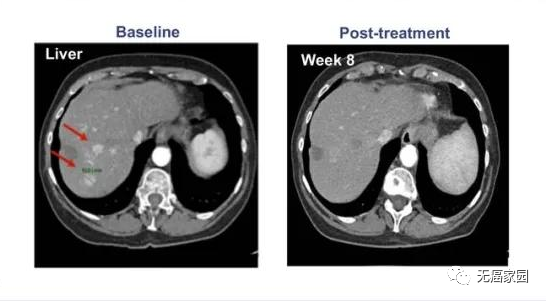

在接受治疗的患者中没有出现细胞因子释放综合征(CRS),也没有神经毒性的迹象。疾病控制率为60%,缓解持续时间为27.7个月。患者的中位OS为33.1个月(典型案例如图所示)。

该患者中观察到肝脏肿瘤的大小显著减少>30%并维持了30个月